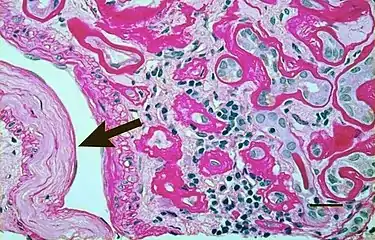

Micrograph showing renal arterial hyalinosis – pink ring right-of-centre. PAS stain.

In benign nephrosclerosis, the changes occurring are gradual and progressive, however, there can be sufficient kidney reserve capacity to maintain adequate kidney function for many years.[10] The large renal arteries exhibit intimal thickening, medial hypertrophy, duplication of the elastic layer. The changes in small arterioles include hyaline arteriolosclerosis (deposition of hyaline, collagenous material), which causes glomerular collapse (wrinkling and thickening of capillary basement membranes and collapse of capillary lumen) and solidification (glomeruli exhibit sclerosis and increase in mesangial matrix). The degree of scarring correlates with the degree of glomerular filtration deficit.